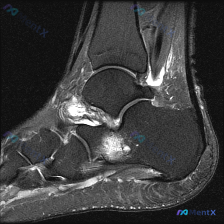

看到这个有意思的病例,整理了完整的分析思路分享给大家。 病例核心影像信息 这是一张踝关节MRI矢状位T1加权图像,原始疑问是观察到「软组织液体」,系统影像评估结果如下: 1. 骨性结构:各骨皮质连续,无骨折、骨质破坏,骨髓信号均匀,关节对位正常,关节面光滑,无明显骨赘或软骨下囊肿 2. 韧带肌腱:跟...